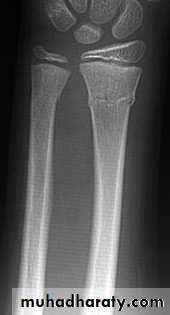

18Torus fracture